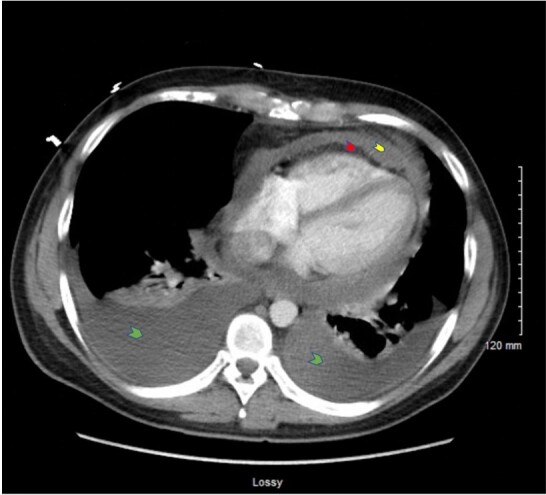

原发性心脏肿瘤很少见。心脏肉瘤是最常见的恶性心脏肿瘤。这些肿瘤的预后很差,总生存期中位数为 25 个月。临床特征包括呼吸困难、心律失常、心包积液、心力衰竭和心脏性猝死。诊断通常具有挑战性。因此,对于标准疗法无效的非典型表现,除了临床高度怀疑外,心脏成像检查也起着重要作用。超声心动图、计算机断层扫描和心脏磁共振成像对确诊至关重要。手术、化疗和放疗等多模式治疗比单独使用其中任何一种模式都能提高疗效。我们描述了一例感染 COVID-19 的 30 岁男性患者的病例,该患者反复出现出血性心包积液,标准治疗无效,最终在活检发现诊断结果并使用 PET-CT-FDG 扫描进行分期后被确诊为心包血管肉瘤。我们的病例再次强调了在发病早期考虑恶性病因的重要性,尤其是在炎性细胞学诊断为积液的情况下,仍反复出现出血性积液时。它还强调了心脏 CT 和 MRI 在确定位置和扩散情况以及计划进一步治疗方案中的重要地位。如果早期诊断,采用多模式方法可延长估计的存活时间。

Primary cardiac tumors are rare. The cardiac sarcomas are the most common malignant cardiac tumors. These tumors have a dismal prognosis with an overall median survival of 25 months. Clinical features include dyspnea, arrhythmias, pericardial effusions, heart failure, and sudden cardiac death. The diagnosis is often challenging. Therefore, the cardiac imaging workup plays a central role in addition to a high clinical suspicion in the setting of atypical presentations that do not respond to standard therapies. The echocardiography, computed tomography, and cardiac MRI are crucial in clinching the diagnosis. Multimodal treatment with surgery, chemotherapy, and radiotherapy has been shown to improve outcomes, as opposed to using either of these modalities alone. We describe the case of a 30-year-old gentleman with COVID-19 infection who developed recurrent hemorrhagic pericardial effusions refractory to standard treatment and was eventually diagnosed as a case of pericardial angiosarcoma after his biopsy revealed the diagnosis and staging was performed using PET-CT-FDG scan. Our case re-emphasizes the importance of considering a malignant etiology early in the course of the disease presentation, especially in recurrent hemorrhagic effusions despite an inflammatory cytologic diagnosis of fluid. It also highlights the place for cardiac CT and MRI to ascertain the location and spread and to plan the further course of treatment. If diagnosed early, the estimated survival time can be prolonged by instituting a multimodal approach.